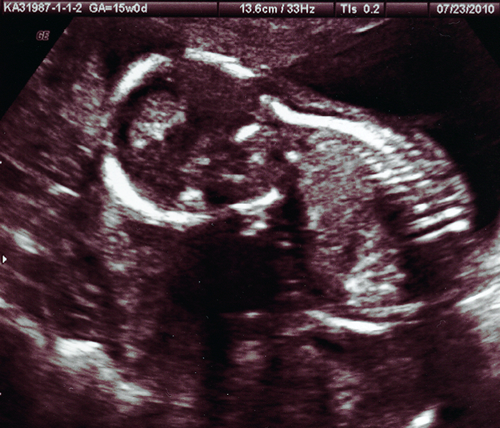

us_3

profile at 15 weeks